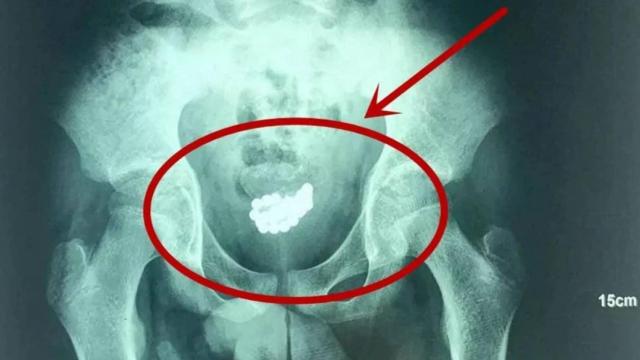

Andrología